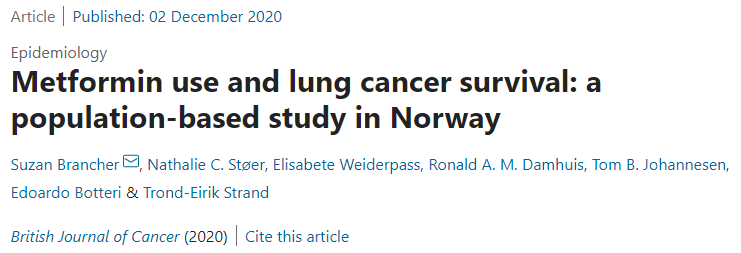

何医生介绍,三代EGFR-TKI伏美替尼由于化学结构上的优化,具备提高药物浓度而不增加副反应的可能,国内外有相似的研究报道。因此,建议李先生开始口服“双倍剂量伏美替尼”靶向治疗。令人欣喜的是,1个月后复查,李先生肺部及肝脏转移灶较前明显退缩,疗效评价达到部分缓解。

目前,李先生仍在口服“双倍剂量伏美替尼”治疗,肿瘤控制良好,已经维持稳定近一年,且并未有副作用,目前患者生活质量良好。

近年来,何志勇主任团队在双倍剂量伏美替尼治疗三代EGFR-TKI耐药的临床实践中,做了临床层面的探索,并总结了临床经验。近2年来,团队共应用双倍剂量伏美替尼18例,其中,3例是初治脑转移患者,15例是三代EGFR-TKI耐药且经历多线治疗后的患者,治疗都能达到不同程度的肿瘤缩小,总体缓解率为86%(13/15),中位疾病缓解时间为4个月,最长的超过17个月。

另据介绍,三代EGFR-TKI耐药后肺癌患者的治疗,是目前临床上的难点和热点。近年来,何志勇主任团队致力于在临床中探索不同的行之有效的策略。除了双倍剂量伏美替尼,团队还采用节拍治疗克服三代EGFR-TKI耐药,总结了28例患者的临床数据,疾病控制率达到89.3%